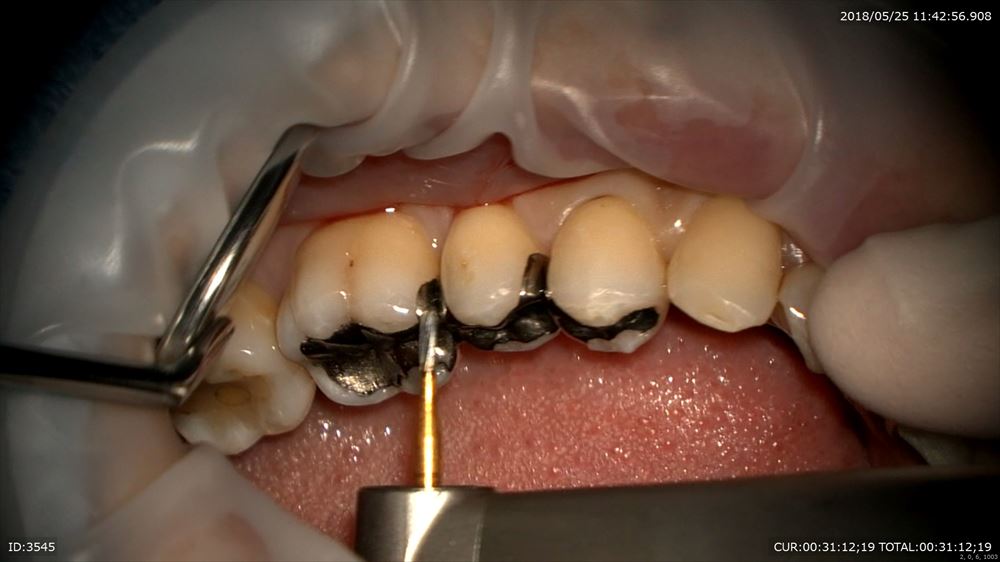

クラックの修復。

秋山勝彦先生にご指導のお蔭でこの様にマイクロスコープですべて直視下でできます。

6番の遠心見えます。

だから丁寧な形成が可能。両手が使えるから。

歯茎に1mmも触らずにできるから血もでません。無痛!!

このように当院では秋山勝彦先生が開発されたマイクロエンドスコーピックテクニックを駆使し治療しています。